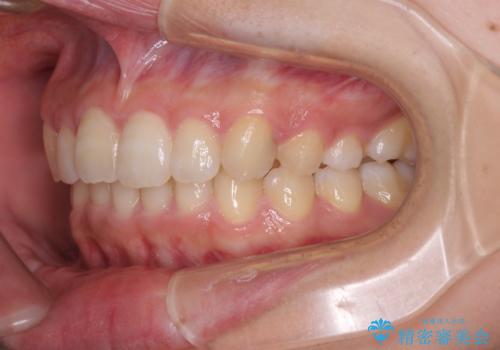

奥歯の倒れた歯を改善 インビザラインでの矯正治療

- 前歯のデコボコと奥歯の不正咬合を気にして来院された患者様です。

左右の大臼歯が全て鋏状咬合(シザーズバイト)になっており、治療が難航することが予想されましたが、インビザラインにより治療を行うこととしました。

最難関と思われたシザーズバイトは比較的短期間で解消されました。

しかし、治療中に2度の出産を経験され、治療期間は長くなってしまいましたが、咬みやすく、清掃しやすい歯列を獲得することができました。